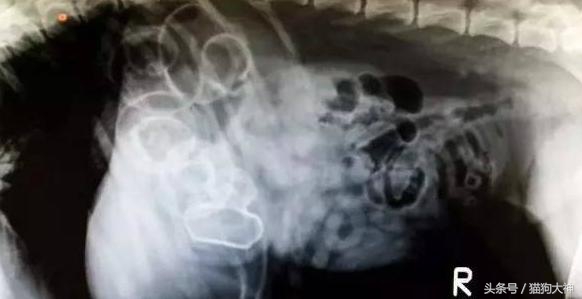

这是一只12岁柯基的胃,由于患上的异食癖,吃了一堆家里盆栽里的土和小石子,把胃都塞满了。这不是一天两天造成的,吃下一堆不能消化的东西狗狗一般会食欲不振,没有精神或排泄困难等表现,如果主人早点注意到,就不会这么严重了。